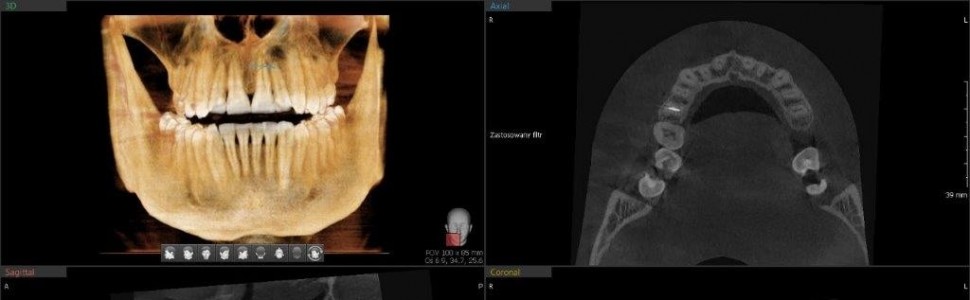

Uniknąć skalpela – endodontyczna regeneracja kości na podstawie przypadków z 3-, 5- i 6-letnich obserwacji

Artykuł przedstawia kilkuletnie (3-,5-,6-letnie) obserwacje zębów leczonych endodontycznie ze zmianami okołowierzchołkowymi o charakterze torbieli z użyciem różnych technologii oraz narzędzi – zaczynając od złotego standardu, jakim jest aktywacja płynów płuczących tj. NaOCl, EDTA/CA, NaCl, poprzez użycie narzędzi ultradźwiękowych, kończąc na zastosowaniu najnowocześniejszej techniki aktywacji płynów za pomocą lasera Er:YAG w połączeniu z technologią SWEEPS. Zastosowanie na każdej z wizyt wymienionych procedur doprowadziło do uzyskania całkowitego wygojenia zmian okołowierzchołkowych, co pozwoliło uniknąć leczenia mikrochirurgicznego (resekcja) lub chirurgicznego (ekstrakcja).